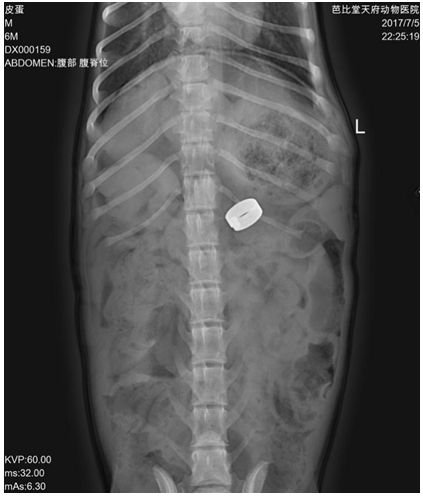

X光可见胃内有高密度一场团块,肝脏偏小,胃轴偏移。

常规备皮,从剑状软骨至脐孔腹中线切开皮肤和腹壁,切除镰状韧带。门静脉-后腔静脉短路的动物需要在后腔静脉入肝处分离,找到短路血管,用弯止血钳轻微提起,留置渐缩环,大小刚好合适,然后填塞钥匙(key)。然后观察胃部,小肠以及胰腺表面血管5-10分钟是否出现发绀、动脉搏动增强、血管明显凸起等,这些都是门静脉高压的表现,若出现,应更换大一号渐缩环,之后再观察,确定无明显异常。需要在肠系膜静脉造影,确认渐缩环在短路血管上,再还纳脏器常规关闭腹腔。